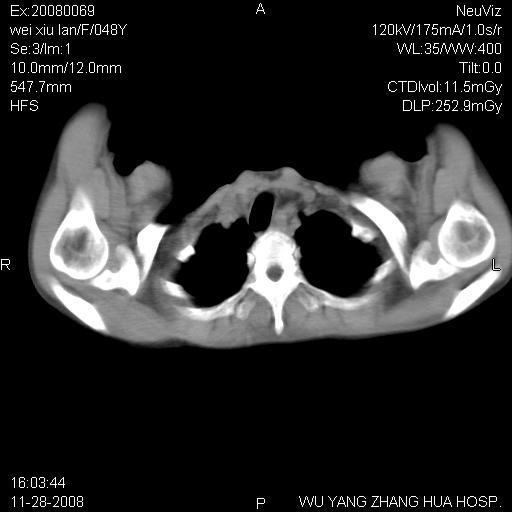

标题: CT16847:女,48岁,咳嗽,发热两日,平常偶有上腹部不适。 [打印本页]

标题: CT16847:女,48岁,咳嗽,发热两日,平常偶有上腹部不适。

能否考虑食管裂孔疝?请老师们多多指教。

胃、脾脏及部分肠管明显升高,并压迫心脏移位,

首先考虑:左侧膈疝。

左侧胸腔内见胃肠及脾脏影

支持膈疝

左膈顶及肋膈角均上移,膈面光滑,考虑左膈肌麻痹